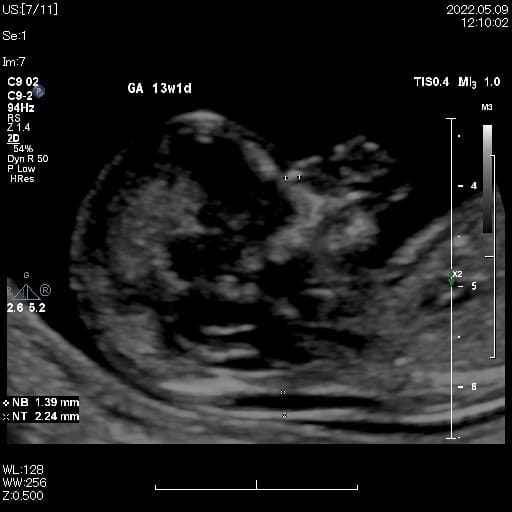

母と子のまきクリニック(Mother and fetus Maki Clinic)は、全国でも数少ない『出生前検査』の専門クリニックで【NIPT認証施設】です。妊婦健診や一般不妊治療、婦人科では小児期から、10~20代では将来を考えた『プレコンセプションケア』、更年期まで様々な女性の健康をサポートしています。 出生前検査の中でも、実施できる施設の少ない『胎児超音波精密検査(胎児ドック)』は、妊娠初期から可愛い赤ちゃんの様子や4D超音波を見て頂きながら、多くの先天性の病気のチェックができ、当日のうちに結果がでる検査です。 ・母体血による検査(NIPT・コンバインドテスト;オスカー検査)<日本医学会NIPT認証施設> ・胎児超音波精密検査(プレドック、初期・中期・後期胎児ドック)<英国FMF超音波資格> ・安全迅速な確定診断(絨毛検査・羊水検査による染色体・遺伝子検査) ご家族で初めて赤ちゃんに出会える!当院ならではの感動の出生前検査です。検査結果に合わせて赤ちゃんをしっかり診させていただき、尊い命を大切に育みながらご家族一緒にマタニティライフを楽しんで頂けるよう願っています。

出生前診断とは、妊娠中の胎児が何らかの疾患に罹患しているかどうかを検査して診断することを指します。出生前検査は赤ちゃんとご家族のための検査です。 出生前診断を行う目的は、あらかじめ出生前に胎児を診断することで、生まれてくるお子さんに病気が予測される場合には、妊娠中から適切な施設を選び、管理を行い、スムーズな治療につなげられ、適切な療育環境の提供ができます。 胎児の疾患の診断や胎児の健康状態の評価を行う出生前診断は、大きく非確定検査と確定検査に分かれます。 非確定検査とは、NIPTや母体血清マーカ―検査、超音波胎児ドックなどです。他に胎児CTや胎児MRIなどで、精密検査を行うこともあります。 確定検査とは、絨毛検査・羊水検査で染色体の数や構造を調べる検査です。この検査では、サイトメガロウイルスや風疹ウイルス、トキソプラズマなどの胎内感染を調べることもあります。 出生前診断では、実際に受ける前に遺伝医療の専門家などによる遺伝カウンセリングを受ける事が望ましいとされています。